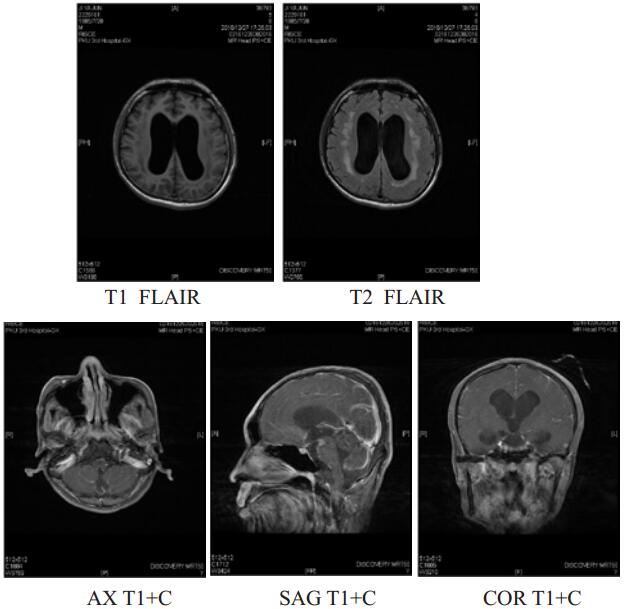

患者,男,31岁,既往体健。因“间断发热、咳嗽10 d,昏迷16 h”于2016年12月9日入院。患者2016-11-30无诱因出现咳嗽、发热,抗感染治疗3 d后,症状好转。2016-12-6患者再次出现上述症状,最高体温38℃,伴头痛。2016-12-8 19:31于本院就诊期间出现意识模糊,瞻妄,次日02:15患者深昏迷,呼之不应。查体:体温38.5℃,脉搏131次/min,呼吸29次/min,血压126/56 mmHg(1 mmHg=0.133 kPa), 心、肺、腹未见异常。专科情况:深昏迷,双侧瞳孔不等大,左侧d=5.5 mm, 右侧d=6.0 mm, 双侧对光反射消失,疼痛刺激无反应,角膜反射未引出,脑神经查体不合作,四肢肌力查体不合作,双上肢肌张力高,双下肢肌张力正常,双侧膝、跟腱反射亢进,踝阵挛,颈强直,克氏征阳性、布氏征阳性。颅脑CT示双侧侧脑室低密度影,颅内感染?双侧侧脑室扩张。血常规:白细胞15.43×109/L,中性粒细胞百分比4.62%;降钙素原3.74 ng/mL, 12月9日行腰椎穿刺抽出淡黄色微混脑脊液,压力>300 cmH2O(1cmHg=0.098kPa), 脑脊液常规:细胞总数864 ×106/L,白细胞818×106/L,多核细胞80%,单核细胞20%,生化:氯113.3 mmol/L,葡萄糖1.00 mmol/L,总蛋白258.0 g/L,革兰染色、墨汁染色、抗酸染色阴性,脑脊液培养结果阴性。血培养结果示:肺炎链球菌。诊断为化脓性脑膜炎,病原菌为肺炎链球菌。给予降颅压,抗感染治疗后,症状好转,2016-12-12患者疼痛刺激有反应。2016-12-20神志转清,可按指令发出动作,但遗留有双侧动眼神经损伤,表现为双侧瞳孔散大,双侧对光反射消失,双侧眼睑下垂,左侧明显,双侧瞳孔各方位(除外展位外)运动不良;此外,合并双侧视神经、左侧面神经损伤,表现为无光感,左侧额纹消失,左侧鼻唇沟略浅。2016-12-26患者恢复部分光感,但视野缺损,无法分辨颜色。双侧动眼神经损伤及左侧面神经损伤未见明显改善,查体脑膜刺激征仍阳性。2016-12-15复查颅脑CT较前无明显变化。2016-12-27颅脑磁共振示脑积水,颅底感染,考虑患者动眼神经及其余脑神经损伤与高颅压压迫脑神经及颅底感染侵及脑神经有关,建议患者外院行脑室穿刺引流术进一步治疗。

2 讨论肺炎链球菌目前为成人化脓性脑膜炎最主要病原菌,大约占到所有病原菌的50%~80%[1-2]。Jit[3]研究提示肺炎链球菌脑膜炎出院患者中,30%~40%的患者都有后遗症,包括智力受损、瘫痪、癫痫发作、听力受损。这些损伤可能与炎症致血管改变导致的脑梗死,脑出血,脑脓肿,血管炎,血栓形成有关[2, 4]。而肺炎链球菌脑膜炎引起动眼神经损伤及其他脑神经损伤的病例极少。复习文献,通常动眼神经损伤考虑以下几方面原因:①颅内损伤,通常由于支配动眼神经核、动眼神经副核的血管发生血管炎或血管痉挛致动眼神经损伤。②颅外损伤,通常与高颅压压迫脑神经有关,常同时涉及第二、三、六、七、八对脑神经,这些脑神经均穿过蛛网膜下腔区域。③颅底感染很容易侵及脑神经,同时晚期形成颅底蛛网膜广泛粘连影响脑脊液回流,这在结核性脑膜炎及隐球菌性脑膜炎中多见,而肺炎链球菌性脑膜炎很少累及颅底感染[5-7]。该患者起病急,临床表现典型,结合病史及辅助检查,考虑化脓性脑膜炎诊断明确,病原学考虑肺炎链球菌。但患者意识恢复后逐渐出现动眼神经、面神经、视神经等多对脑神经损伤。对于该患者,动眼神经损伤同时累及视神经、面神经等多对脑神经损伤,持续脑积水状态,且影像学可见明显的颅底感染,故考虑该患者的脑神经损伤与高颅压状态压迫脑神经及颅底感染侵及多对脑神经有关。最终建议患者行侧脑室穿刺引流、脑室-腹腔分流术等解除高颅压状态。

| 图 2 为2016年12月27日颅脑磁共振,提示脑积水、颅底感染 |